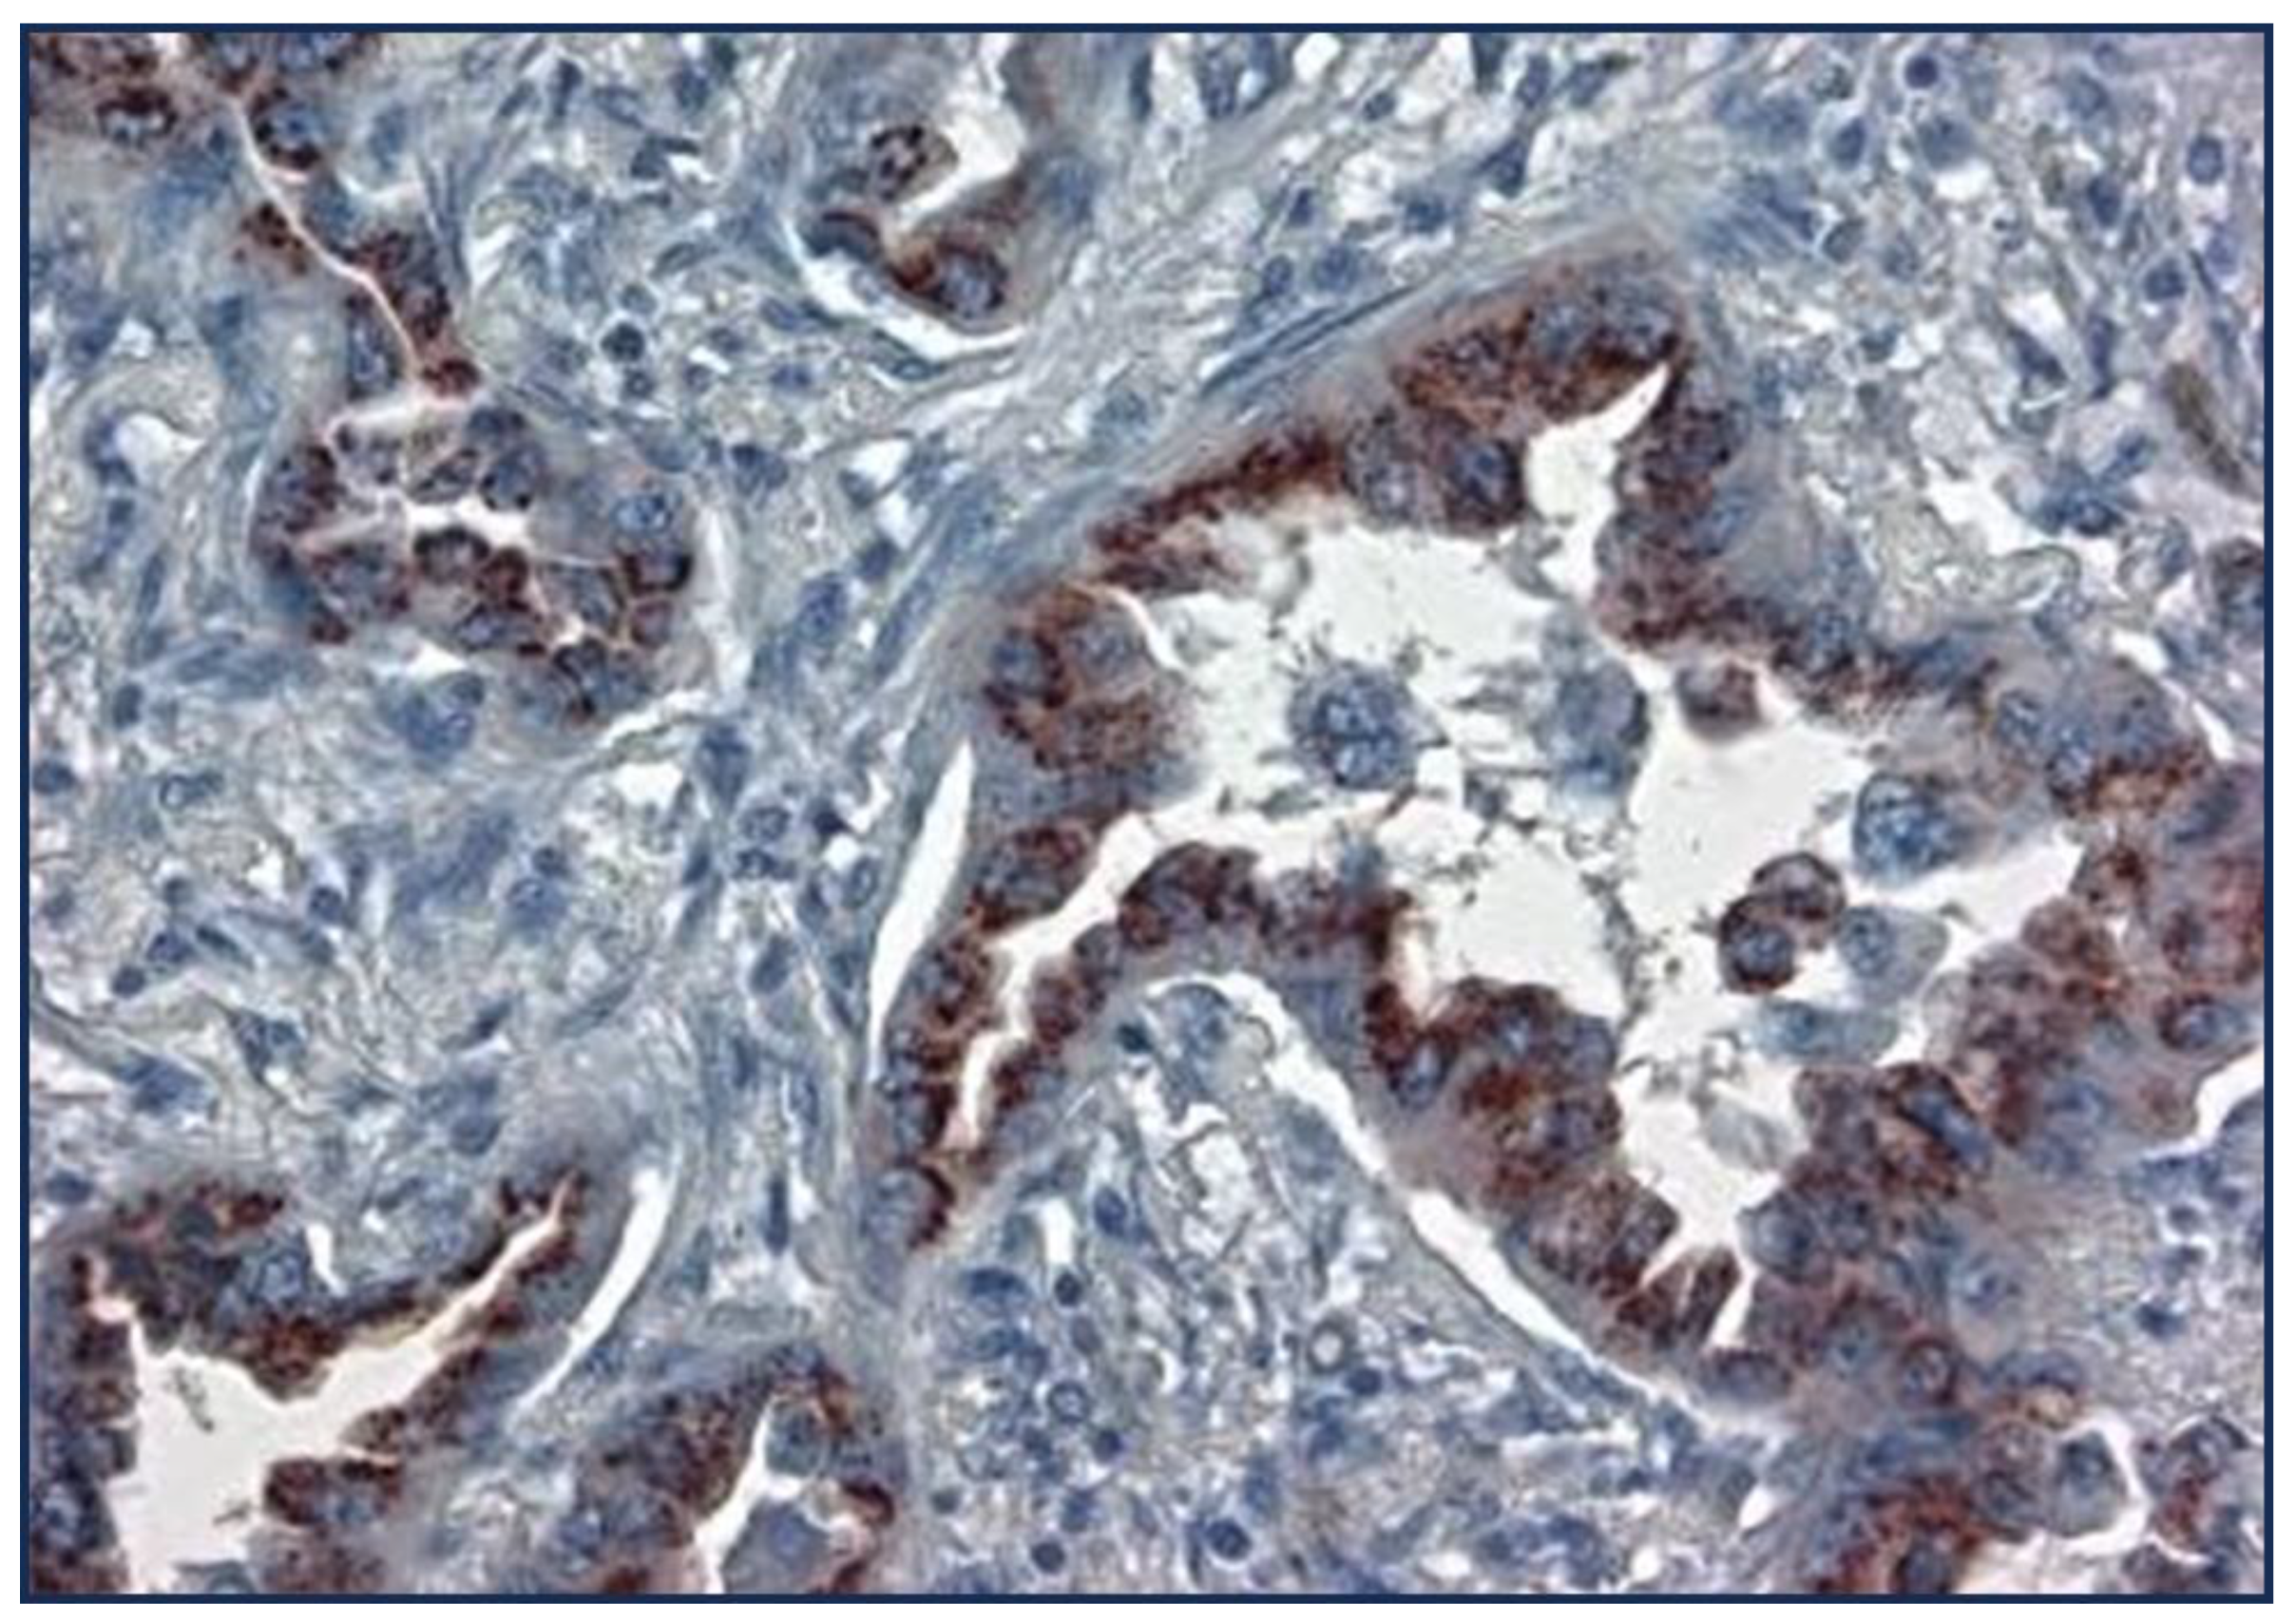

| Cancer Type | Adnab- 9(p87) |

TTF1(Clones) | NE Marker |

%p63/p40 | CK7 (NRecc) |

|---|---|---|---|---|---|

| Lepidic/BA | 67 | N/A | N/A | ||

| AdenoCa | 32 | 80(muc10-15) | N/A | 20-30 | 94-100 |

| Squamous | 6 | N/A | 5-77mean25% | ||

| Large Cell | 0 | 41 (9-85) | 92 | ||

| Small Cell | 22 | 79-100 | |||

| NSCLC | 15 | 10-20 | 68 | ||

| AdenoSquamous | 27 | N/A | 99 | ||

| Papillary | 74 | N/A | |||